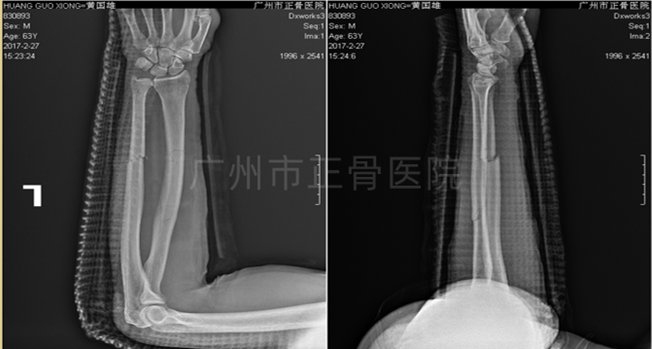

治疗:运用黄氏正骨手法复位骨折并以小夹板外固定,复查X线片提示骨折端位置良好。3天后复查X线见尺骨移位,调整后加石膏托固定,复查X线提示骨折端位线较前改善。1周后复查X线提示骨折稳定。维持石膏、夹板固定,继续复查换药,指导患者适当功能锻炼。6周后,可见轻微骨痂生长。2个月后骨折线部分模糊,2个半月后复查X线提示骨痂生长增多,骨折端稳定,拆除外固定,指导患者循序渐进进行功能康复锻炼。3个月后,患者功能恢复正常。1年后复查X线片,提示骨性愈合。

▲6周后,骨痂增多

▲2个月后,骨折线模糊,拆除夹板